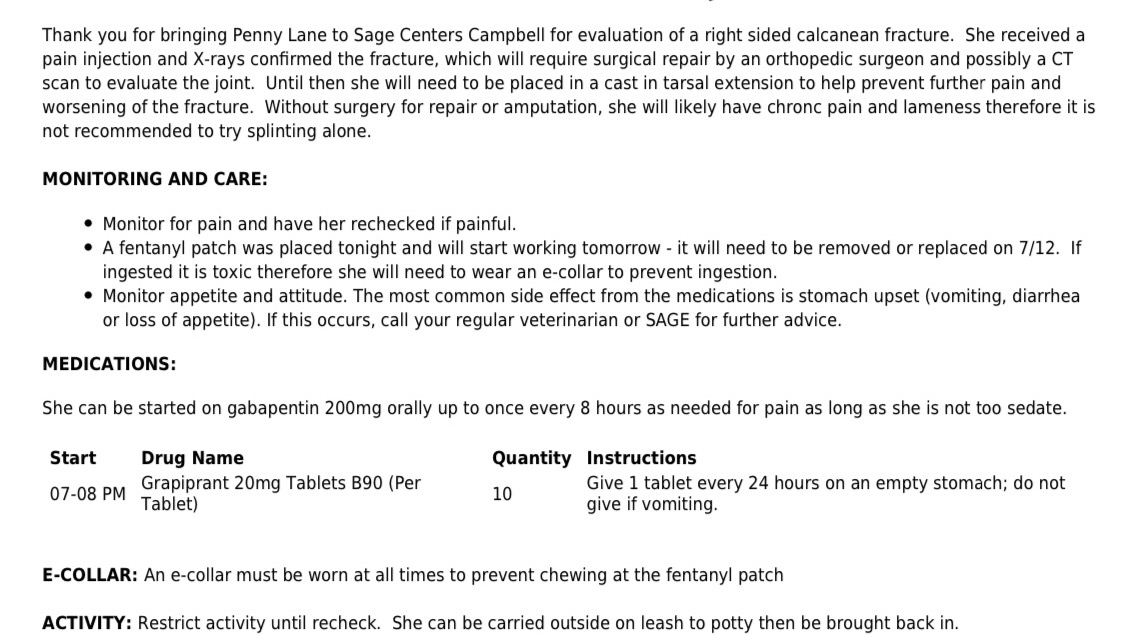

Hey Friends - I rescued a beautiful 5 month old puppy about a month ago. She was abandoned in a parking lot. Yesterday Penny Lane got severely injured playing. She may never be able to walk again unless I can get her the surgery she needs and soon. She is in alot of pain now, but it is being managed with pain meds and ice. It is so precious how much she wants to play still, her personality is still so sweet and affectionate. She is figuring out how to manage with her fractured heel. The vet costs are 8,000$, Every avenue of support can help save her leg please share this with anyone who may be able to contribute and sponser Penny Lane…

She has already expanded my heart SO much within just a month of rescuing her, she has SO much more love to give and has changed my life.

Penny Lane is strong, and healthy other than this injury. She is such an energetic, curious, happy playful 5 month old baby girl! We are so GrateFULL for all your love, support, donations and shares!! Everything will go towards healing her leg and getting her back to enjoying a full beautiful life!